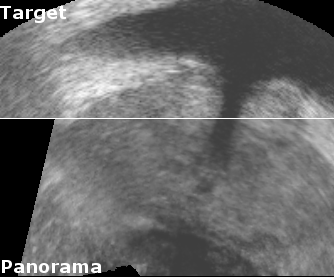

To measure reproducibility and registration success, 10 registrations were carried out for each volume pair from slightly perturbated start points by adding noise of 2mm and 2°. This yielded 10 transformations that approximate the unknown rigid transformation between the prostate in both volumes. The average transformation of the was computed with the method presented in [9]. The euclidean distance error , with being the image center, and the angular error , which corresponds to the rotation angle of , were used to compute the root mean square (r.m.s.) errors and . A registration was considered successful if mm and degrees, and if the result was visually satisfactory when superimposing both volumes in a composite image (See Fig. 2).

Reconstruction accuracy evaluation was more difficult to implement since there is no straight-forward gold standard. In some images, the needle trajectories from previous biopsies were still visible. In these cases, the trajectories were manually segmented, and the angular error between corresponding needle trajectories were used to evaluate rotational accuracy. Also, some patients had significant and clearly visible calcifications inside the prostate. The distances between segmented calcifications were used to determine the translational accuracy. Tab. 1 and Fig. 2 show the results of the evaluations.